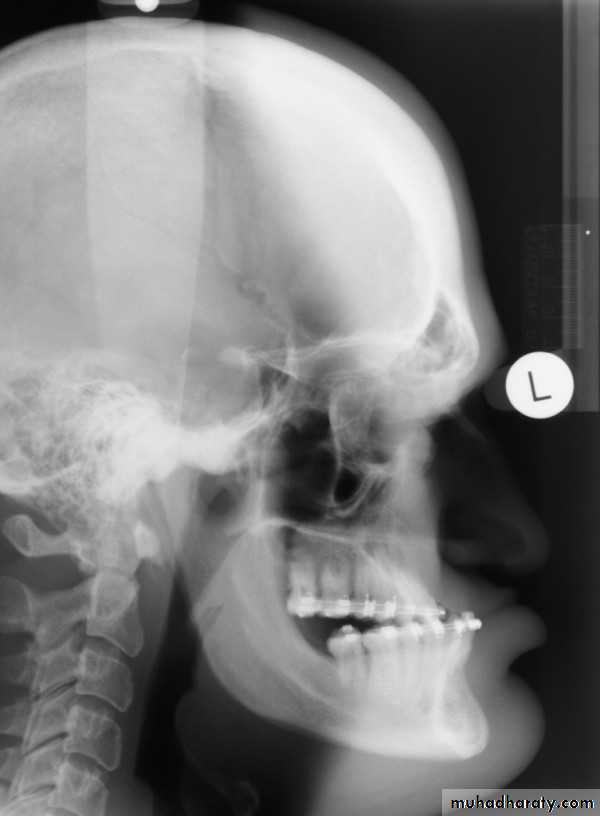

Acromegaly & prognathism

Skull manifestation of the acromegaly

1.Thickening of the skull vault &diplioc space2.Thickening of the posterior occipital tubercle

3.Prognathism

4.Froehead bossing with enlargement of the frontal sinuses also with enlargement of the mastiod air cell .

5.Balloning with Double floor appearance of the sella tursica .